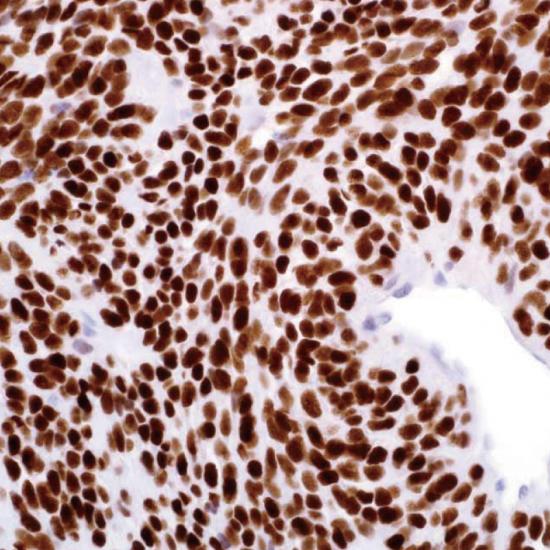

TLE1

TLE1抗體試劑(免疫組織化學) 閩廈械備20180273號

• 陽性部位:

細胞核

• 陽性對照:

滑膜肉瘤

TLE1是TLE多基因家族中的一員,參與造血,神經分化和末梢上皮細胞分化??稍诨と饬鲋斜磉_,在神經鞘瘤和多形性肉瘤中很少表達。TLE1對滑膜內瘤的診斷敏感性達到82%,特異性92%,用于滑膜內瘤的診斷,與EMA、BCL2、AE1/AE3聯(lián)用對診斷滑膜內瘤特異性及敏感性均很高。